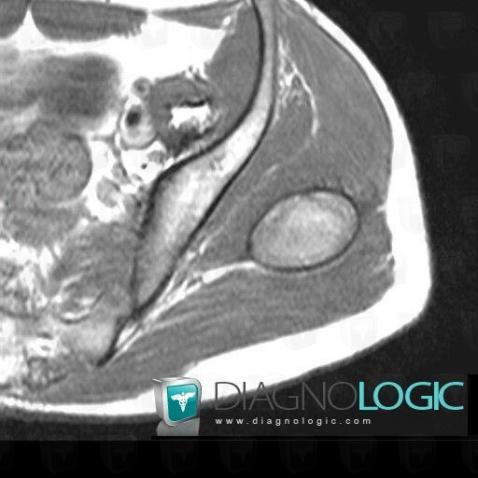

Hematoma, Pelvic Muscles, Other soft tissues/nerves - Pelvis, MRI

Here is the specific information in the key image above:

- Diagnosis Hematoma, Location(s) Pelvic Muscles, with gamuts T1 WI Hyperintense soft tissue lesionOther soft tissues/nerves - Pelvis, with gamuts T1 WI Hyperintense soft tissue lesion